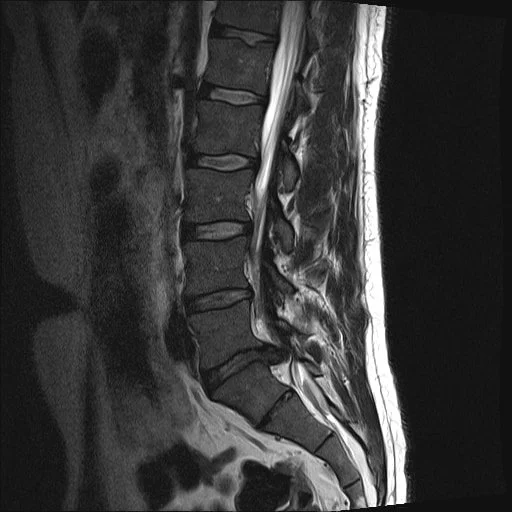

Magnetic resonance imaging (MRI) scan of the lower back spine in black and white.

On this scan, there is advanced degeneration of the bottom disc (L5-S1). Compared with the other discs it is very narrow and there is prominent posterior bulging. The bone adjacent to the disc (vertebral endplate) shows increased brightness which is a sign of disc degeneration (Modic changes).

MRI scan of the lower back showing lumbar vertebrae and spinal cord.

At L5-S1, the back of the disc looks abnormal. This is more than a bulge and is a focal disc herniation. Here, the annulus has split and part of the nucleus has herniated into the spinal canal, compressing the spinal nerves. This type of herniation is called an extrusion. Other types are protrusion and sequestration.

Here, all the discs show advanced degeneration with near-complete loss of height and bulging. The endplates are irregular and show Modic changes. The degeneration has caused the spinal canal to become narrow (stenosis).